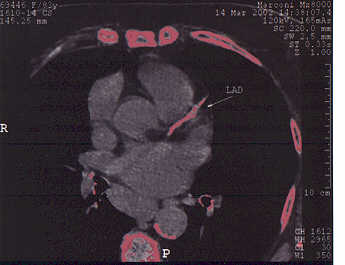

# 3 FL: Avoiding Angiography in an Octogenarian

This turned out to be a good

idea. FL tolerated four months of

NanobacTX well; angina frequency fell from 5 to 1 episode per week, NTG is no

longer required, and FL was able to increase her activity level considerably.

Her CT score fell by 26%, fibrinogen fell by 30 points, and her

cardiac-CRP value plummeted. Following an additional two months of treatment, FL's score

fell an additional 36%, so at the six month point, FL's score has fallen by

53% from baseline. A dobutamine stress echo (chemical stress echo)

demonstrated the old heart attack that we knew about, but no new abnormalities

were brought out. Subjectively and objectively FL improved. The

baseline and six month scans are shown below; with your own eye you can see the

difference in the extent of LAD calcification. FL is going to continue on NanobacTX, aiming for

complete decalcification.